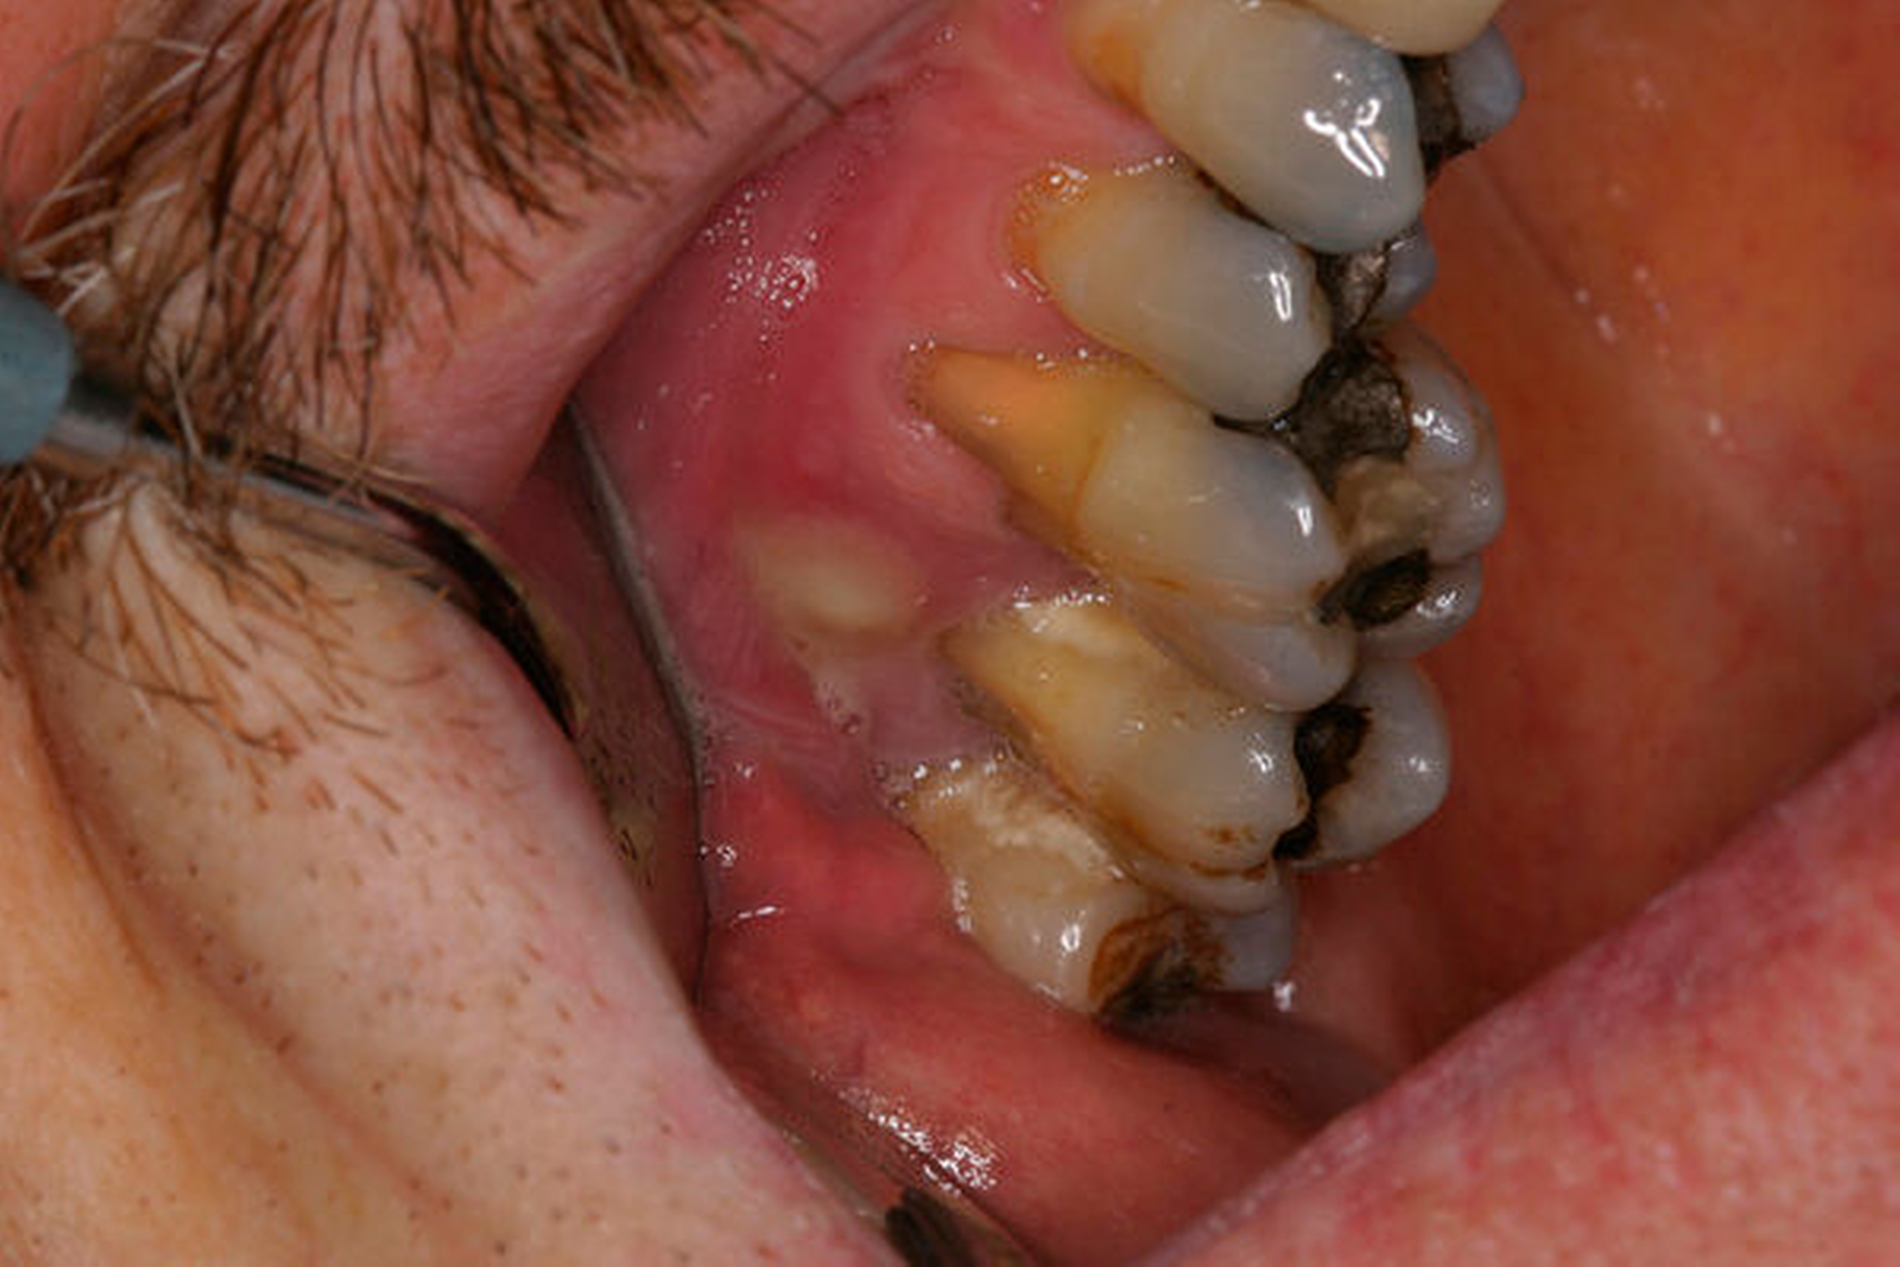

Tiefer kariöser Defekt (Fall Nr. 10)

Eine 53-jährige Patientin stellte sich 2015 mit plötzlich aufgetretenen, starken Beschwerden an Zahn 16 und der Bitte um Abklärung vor. Es erfolgte die klinische und röntgenologische Befundung des Zahnes, der neben einer apikalen Parodontitis auch eine große, fast bis in die Furkation reichende Kronenrandkaries an der mesiobukkalen Wurzel aufwies. Um diesen vorhersagbar versorgen zu können, wurde der Patientin die endodontische Behandlung mit Amputation der mesiobukkalen Wurzel und anschließender Versorgung mittels Vollkrone als Alternative zur Extraktion aufgezeigt. Sie entschied sich für den Zahnerhalt.

So folgte nach der Wurzelfüllung die Amputation der mesiobukkalen Wurzel. Der Zahn wurde nach der Amputation auf Wunsch der Patientin zunächst mit einem Langzeitprovisorium versorgt, das im Verlauf gegen eine definitive Versorgung ausgewechselt wurde. Die Patientin ist seitdem an 16 beschwerdefrei, der Zahn ist stabil und hat eine gute Langzeitprognose.